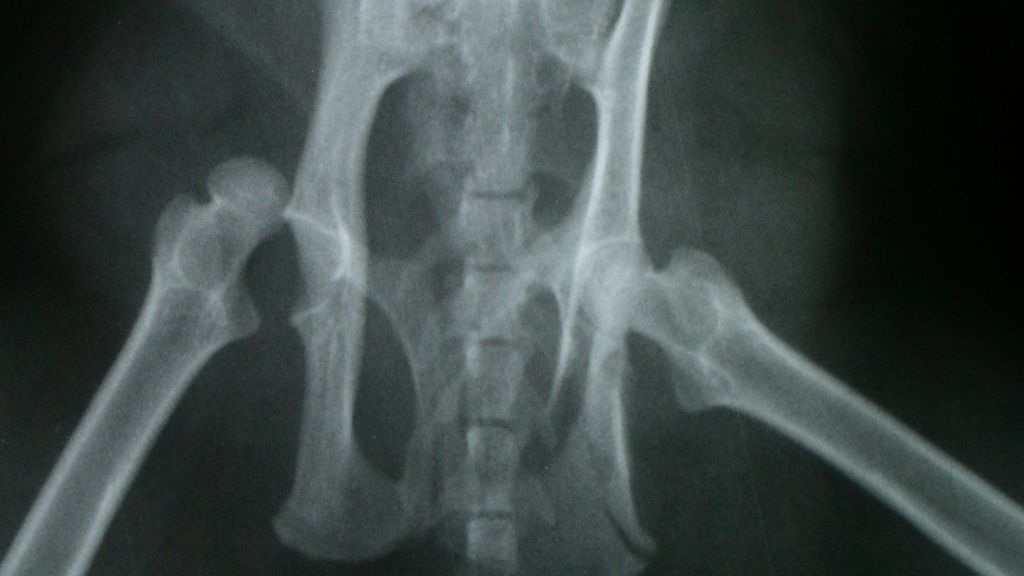

Để xác định chẩn đoán, bác sĩ sẽ chỉ định thêm hình ảnh học như siêu âm (với trẻ dưới 6 tháng tuổi) hoặc X-quang (với trẻ lớn hơn).

Bẩm sinh trật khớp háng (CHD) là tình trạng trẻ sinh ra với khớp háng không ổn định do cấu trúc khớp phát triển bất thường ngay từ giai đoạn bào thai. Bệnh còn được gọi là loạn sản khớp háng phát triển. Khi trẻ lớn lên, mức độ lỏng lẻo của khớp có thể tăng dần.

Trong tình trạng này, chỏm xương đùi có thể trượt ra khỏi ổ cối, thậm chí bị lệch hoàn toàn khi vận động. Theo các nghiên cứu, có khoảng 1/1000 trẻ sơ sinh bị trật khớp háng ngay từ lúc chào đời.